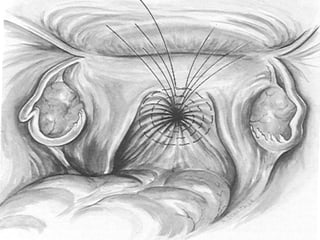

Pubo-cervical fascial defect

Richardson